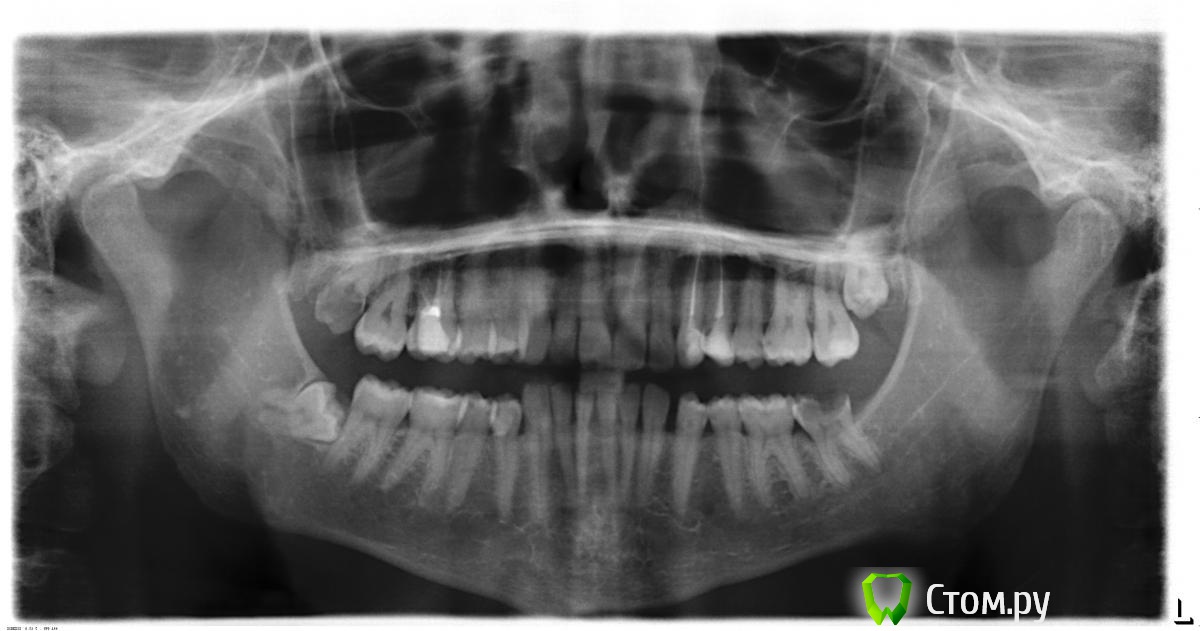

Byke Опубликовано 19 июня, 2014 Автор Поделиться Опубликовано 19 июня, 2014 (изменено) Странно, добавлял снимок до удаления!! Изменено 19 июня, 2014 пользователем Byke Ссылка на комментарий

faity Опубликовано 19 июня, 2014 Поделиться Опубликовано 19 июня, 2014 Странно, добавлял снимок до удаления!!надо теперь после удаления КТ сделать, судя по этому снимку- верхушки корней находятся в проекции нижнечелюстного канала, при травматичном удалении(щипцы) могли сделать компрессию или даже повреждение нерва, чтобы это исключить надо 3D снимок, т.е. КТ.если нижнечелюстной канал не поврежден- значит осложнение после анестезии, пройдет гематома, спадет отек- пройдет болезненность и парестезия(чувство обезболивания)если поврежден- чувствительность начнет восстанавливаться через полгода- год, и не факт что вернется поолностью.сделаете снимок выкладывайте или можете мне в личку написать Ссылка на комментарий